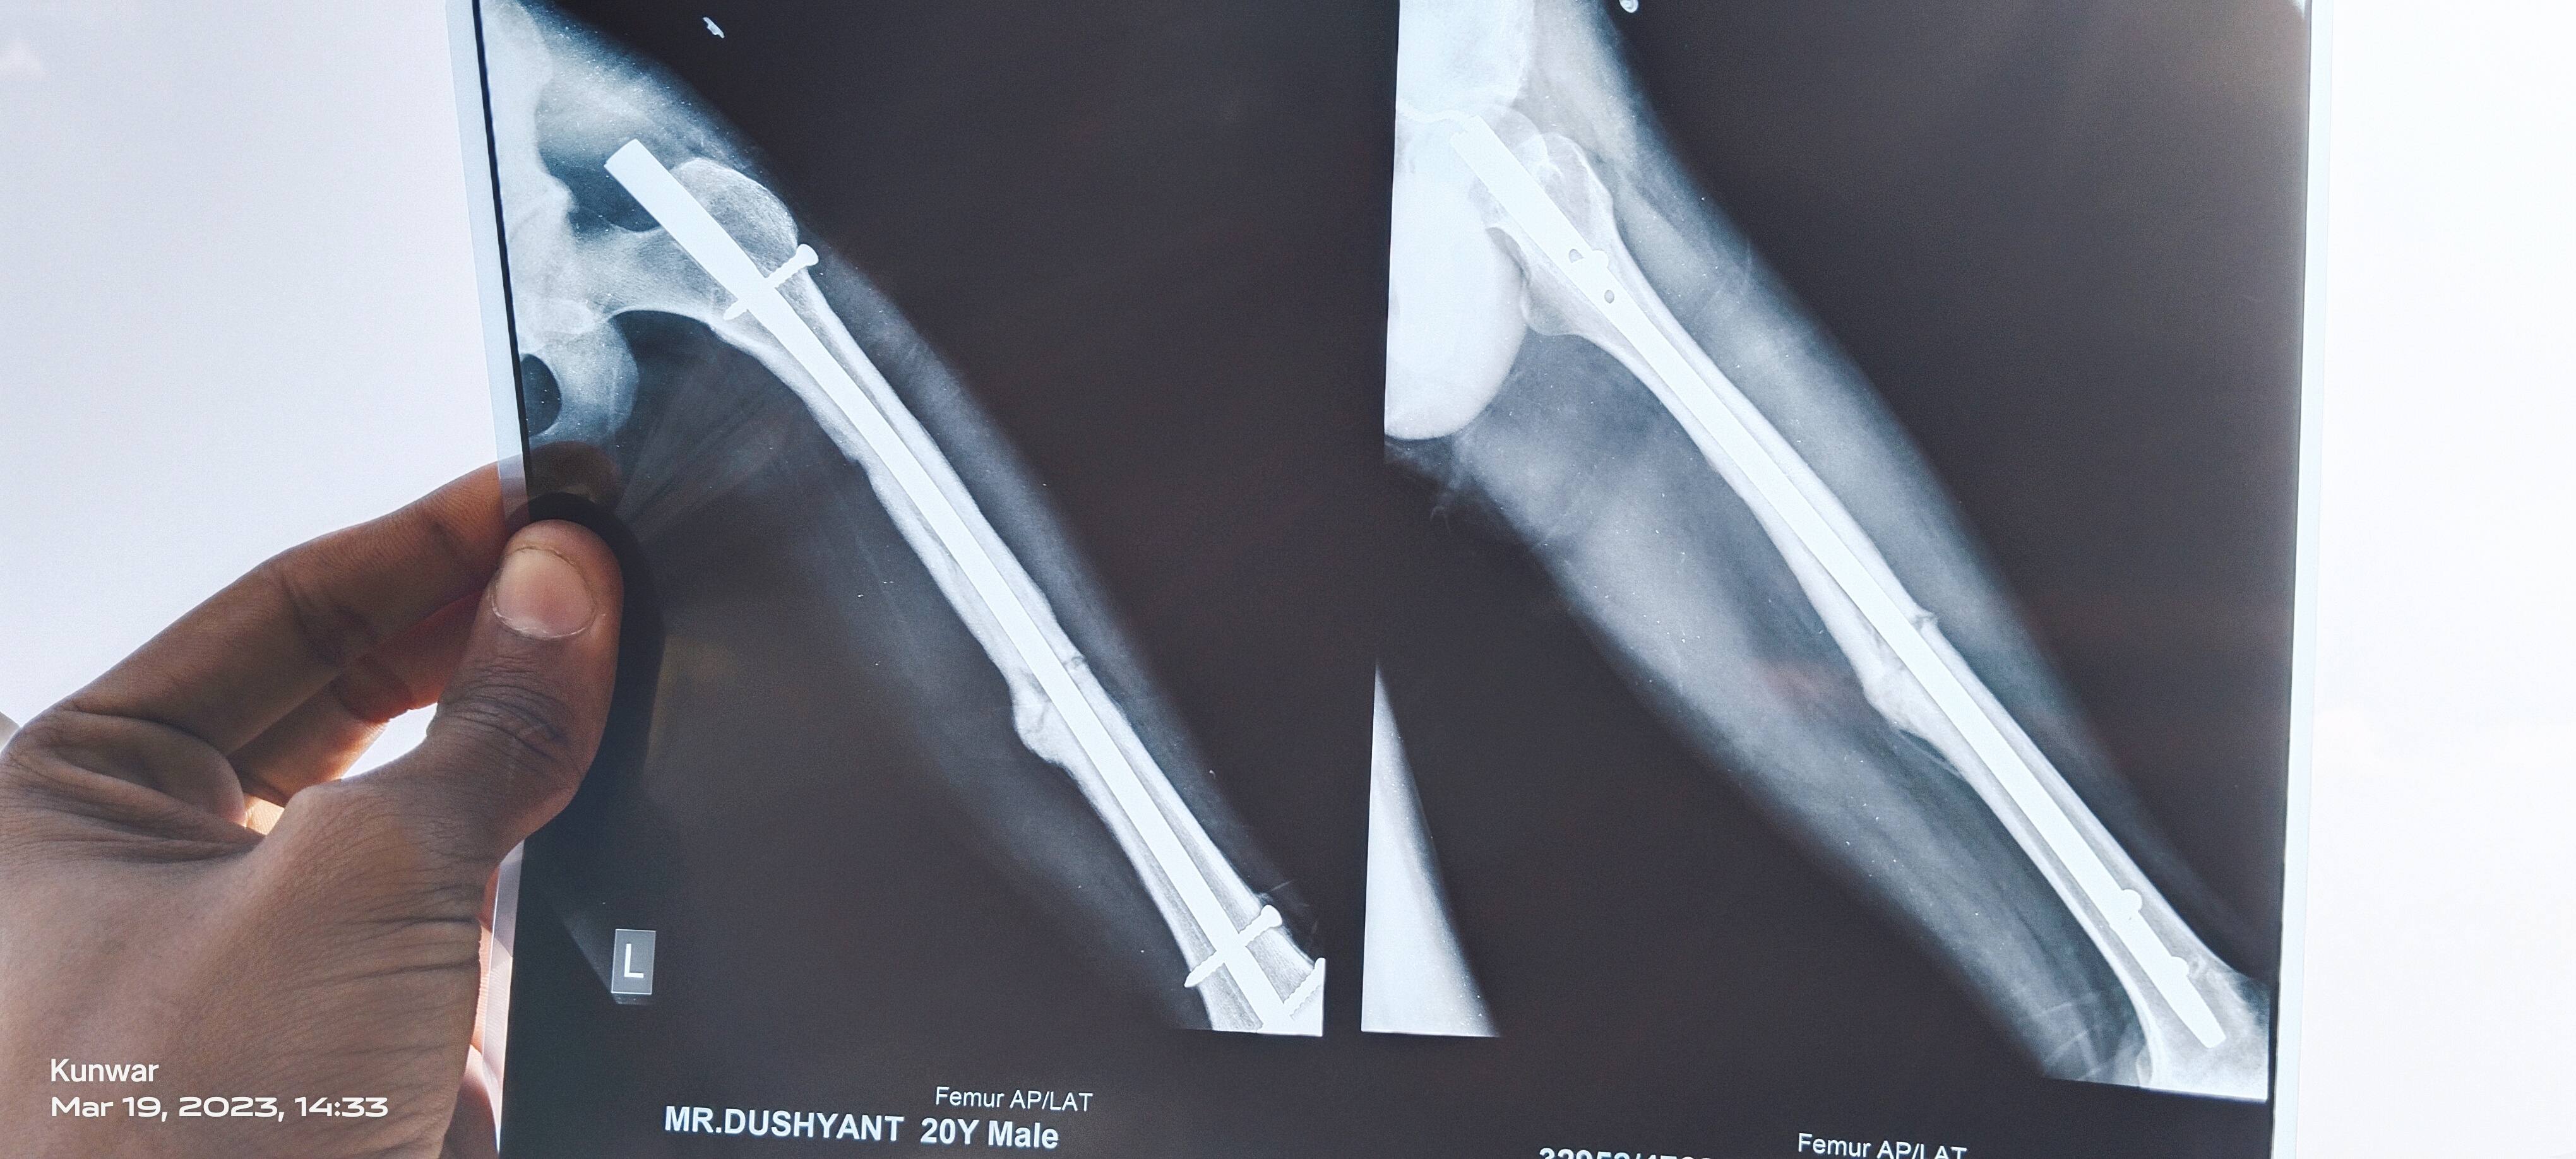

myself Dushyant from palwal Haryana .sir mera 8 august ko femur bone shaft fracture hua tha jisme aur bone displace ho gyi thi air overlap bhi the 10 august ko meri successful surgery hui thi aaj mujhe 78 dsys ho chuke hn i m walking with full weight bearing with walker then how much time this bone takes to heal completely and whenn i am able to walk normal activities likea normal person helo me sir my surgeon is non responsable i come with a great hope to you ?may god bless you a prosperious life

This is my femoral shaft fracture which happened ast year on 8 august 2022 Now its been 1 year Should i remove the implant or not Is there any complication after removal.of implant

Sir this one is x ray on 7 month post surgery what should i do my doc suggest me to remove it after one year what's you suggestion